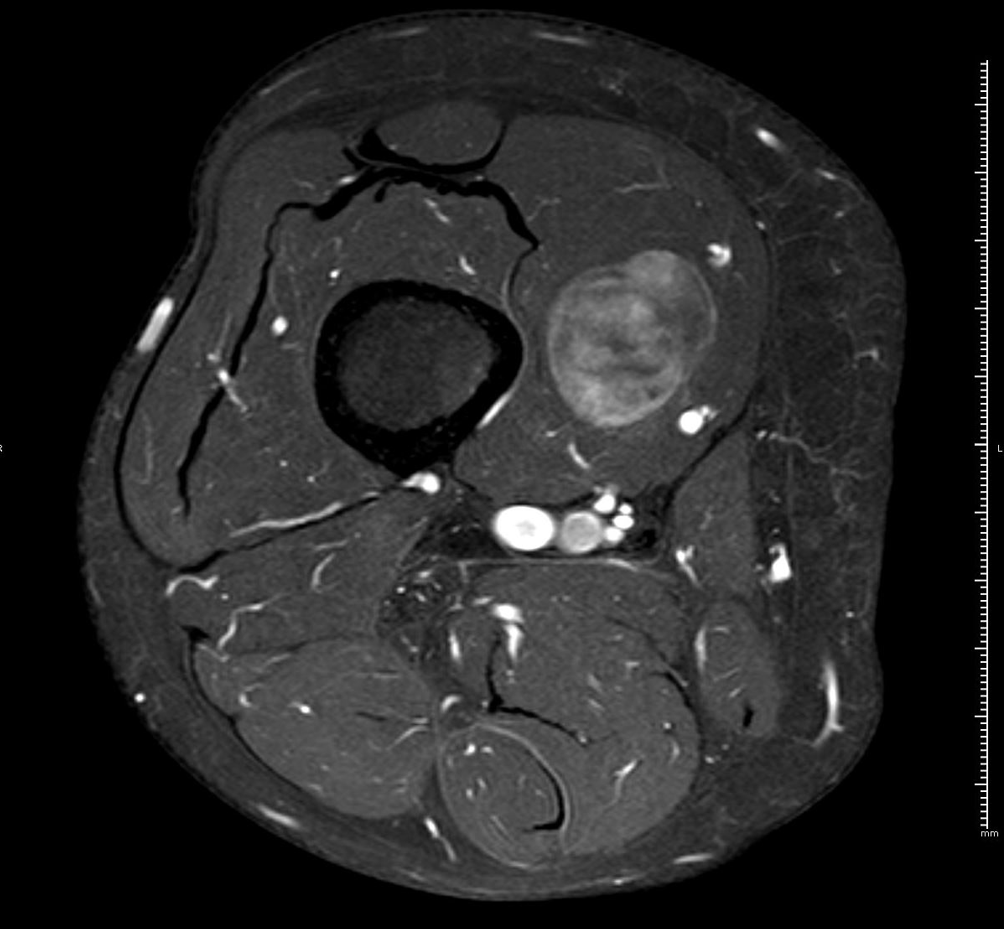

RM axial T1 con supresión grasa y gadolinio iv.

HALLAZGOS RADIOLÓGICOS